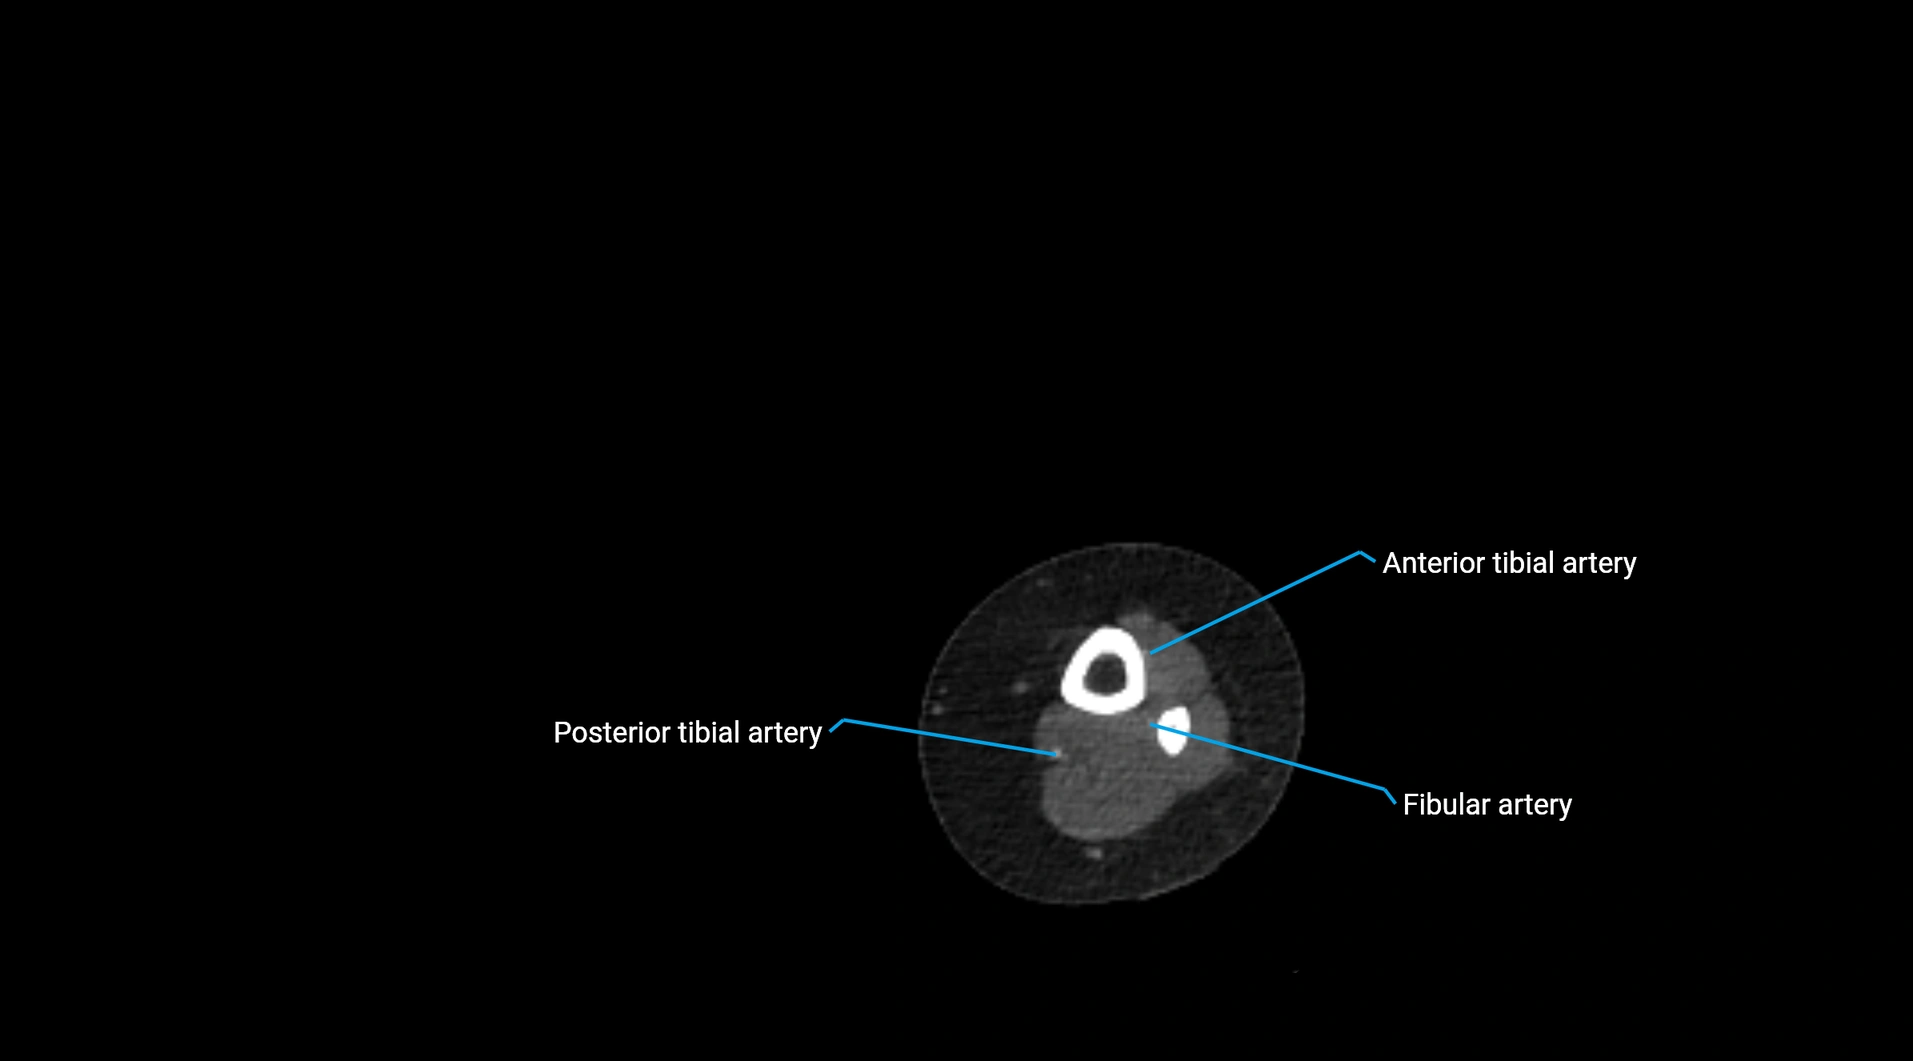

CT Appearance

Non-contrast CT:

• Appears as a tubular soft tissue structure anterior to vertebral bodies

• Calcified atherosclerotic plaques appear as hyperdense foci along the wall

• Useful for screening abdominal aortic aneurysm (AAA) size and mural calcification

Contrast-enhanced CT (CTA):

• Gold standard for abdominal aortic imaging

• Provides excellent detail of lumen, wall, aneurysm, thrombus, and branch vessels

• Multiplanar and 3D reconstructions help in aneurysm measurement, stent graft planning, and dissection evaluation

• Detects acute rupture, traumatic injury, or occlusion with high sensitivity